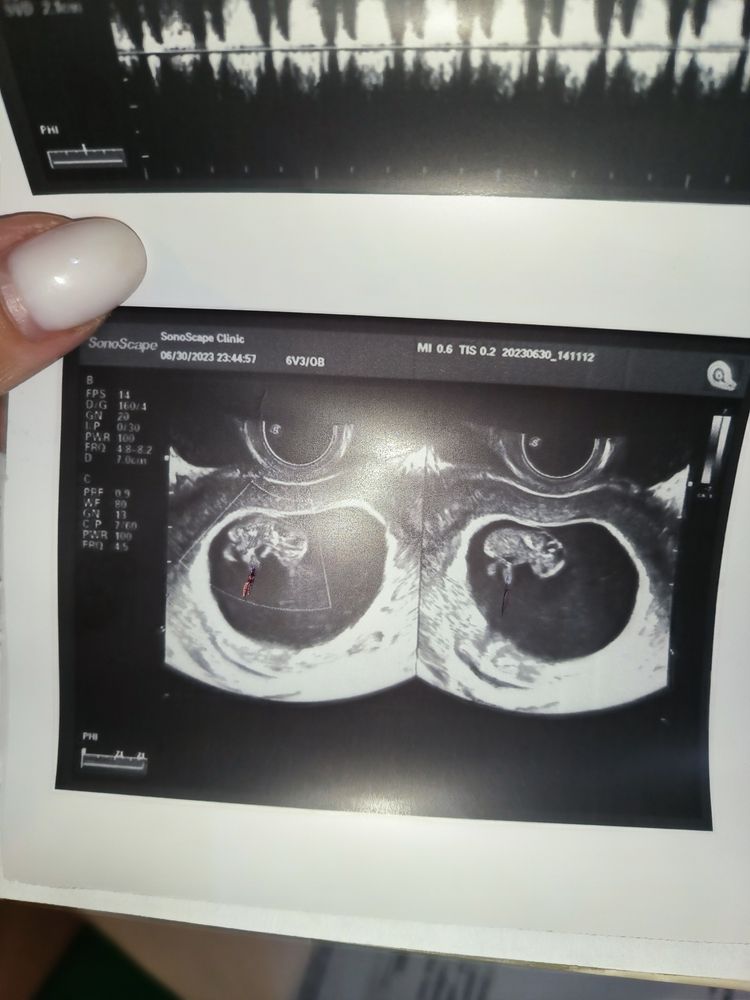

Съездила вчера на УЗИ туда же где 13 дней назад врач поставила двойню(однояйцевая) во вторник в другой клинике нашли только одного лялика, вчера врач после УЗИ выдала такое вот заключение, что это может быть? Даже чсс написала-185 уд мин. Размеры до 7 мм(в прошлый раз она написала что это второй эмбрион) видно ли пуповину в 9-10 недель? По фото вообще как будто это просто нога

Кровоток у второй ляли есть, сердечко стучит, значит догонит по размеру!!! Бывает,что при беременности лоцируется линейное включение повышенной эхогенности, т.е интрамурально-субмукозный узел, но!!!! у него не будет сердцебиения! Ждём развязку!🥰

Насколько я понимаю по заключению - эмбриона увидели два, но второй меньше по размеру (и под вопросом отставание в развитии). Мне кажется, надо наблюдать и ещё раз сходить через неделю. А клиники Фомина в Перми нет случайно? Там очень хорошие узисты

Ксения, и так и так) всяко искали) а тут даже если и второй малыш то получается что за 13 дней он совсем не подрос 🙄